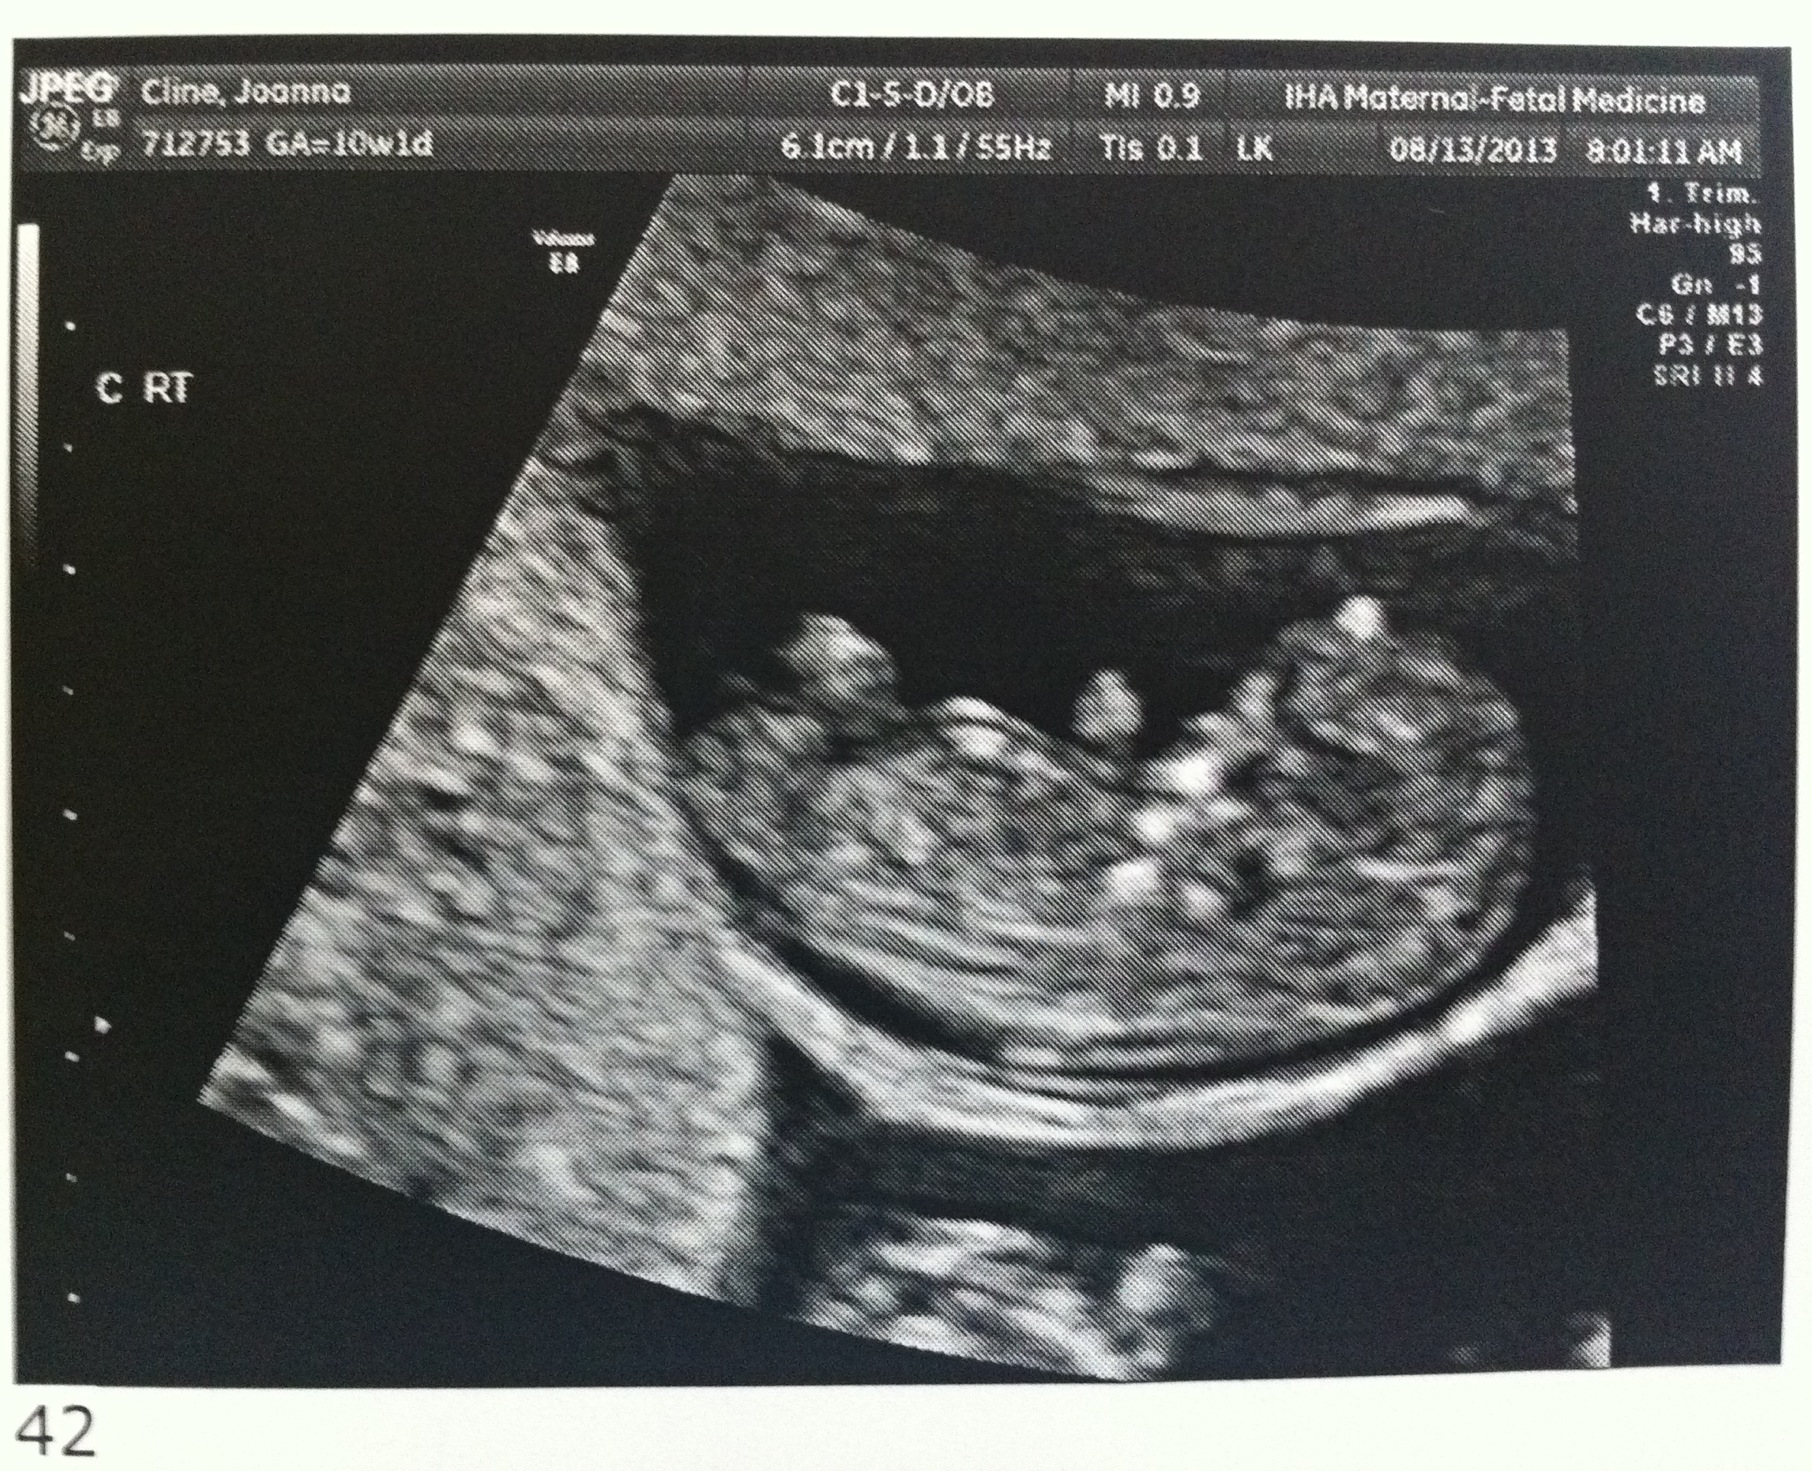

Good morning! I’m 10w1d today and we went for another ultrasound this morning. The u/s tech told us that everything looks exactly as she’d want it to at this point in the pregnancy. The heartbeats are great and they are wiggling around in there!

I’ve attached a few new photos – close ups of each and one group shot. 🙂